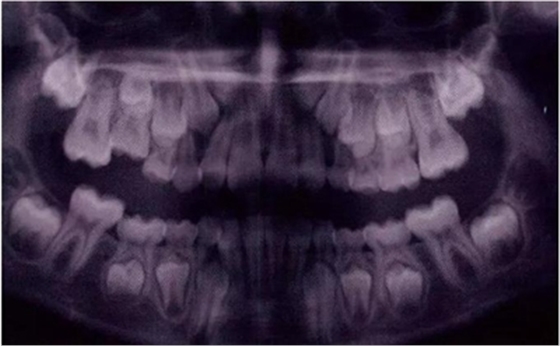

圖11是一張曲面體層片,上面顯示了一名九歲男孩同時(shí)患有55,75,和85的下沉。其55和85 為中度下沉,75為輕度下沉。這幾顆牙都沒(méi)有齲齒,都伴有恒牙胚的存在,并且沒(méi)有鄰牙傾斜和間隙喪失的臨床表現(xiàn)。給予這個(gè)孩子的方案是醫(yī)囑三個(gè)月常規(guī)復(fù)診以觀察監(jiān)測(cè)這些牙的下沉情況。結(jié)果這些牙均未加重至超過(guò)中度下沉,并且全部自然脫落,恒牙正常萌出。

圖11:曲面體層片顯示一名9歲男孩乳磨牙下沉,繼承恒牙胚存在。